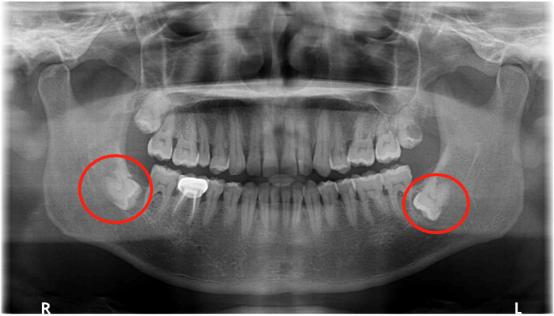

我们通常所讲的会造成严重后果的智齿,都是指下颌智齿。那么可能引起严重后果的下颌智齿又有哪些情况呢?如下图:

近中阻生

水平埋伏阻生

倒置阻生

大家千万注意,长成以上类型的智齿都可能发炎,如果不对它们进行及时的处理,任由它发展下去的话,便会导致很严重的后果。所以对于上述所讲情况的智齿,都应该引起一定的重视,最好尽早将智齿拔除。

如果我们不把上图情况的智齿拔掉,最直接的影响就是智齿旁边的牙可能会被顶坏,导致牙髓发炎需要根管治疗,甚至牙根都可能烂掉,最终无法保留,只能拔除。